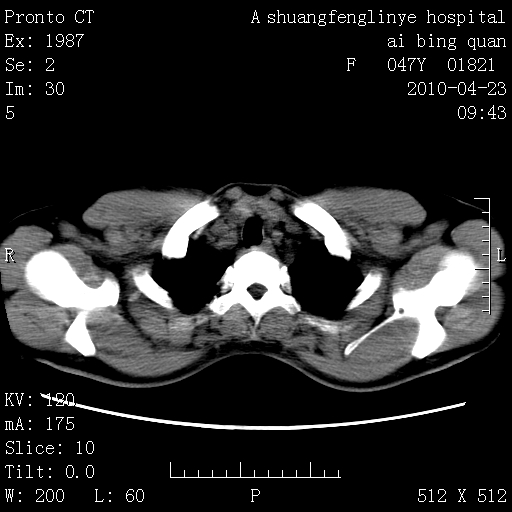

标题: CT25944:胸痛、气短、前几日高烧!肺Ca?请会诊! [打印本页]

标题: CT25944:胸痛、气短、前几日高烧!肺Ca?请会诊!

双肺多发结节,考虑转移瘤,肺癌肺转移不除外

双肺多发结节,部分密度较高,最大结节边缘光滑。临床有“胸痛、气短、前几日高烧”病史。首选考虑:右肺感染性病变!建议积极消炎后复查!